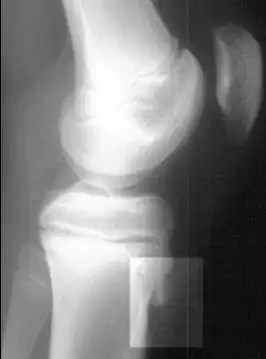

| Radiografia lateral do joelho demonstrando fragmentação da tuberosidade da tíbia, com o tecido superabundante. | |

Os fatores de risco incluem o uso excessivo, especialmente esportes que envolvem correr ou pular. O mecanismo subjacente é a tensão repetida na placa de crescimento da tíbia superior. O diagnóstico é tipicamente baseado nos sintomas. Uma radiografia simples pode ser normal ou mostrar fragmentação na área de fixação.[5]